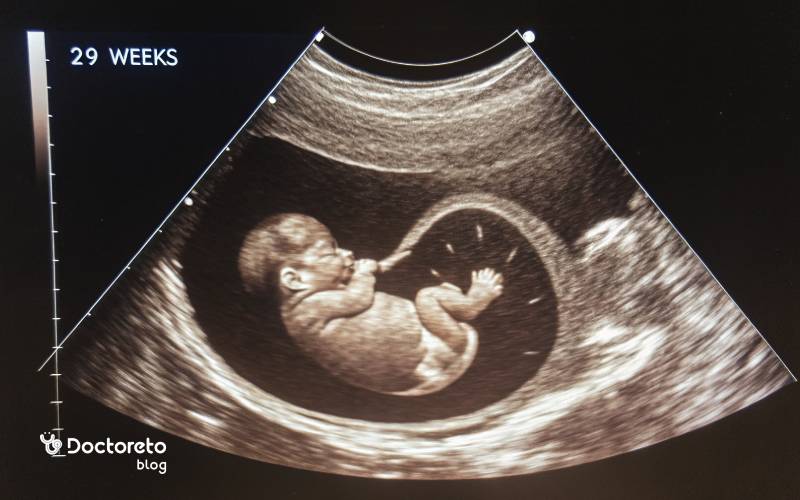

عکس جنین ۲۹ هفته دختر

عکس جنین ۲۹ هفته دختر را مشاهده می‌کنید.

جنین ۲۹ هفته دختر

عکس سونوگرافی جنین در هفته 29

عکس سونوگرافی جنین در هفته 29 را مشاهده می‌کنید.